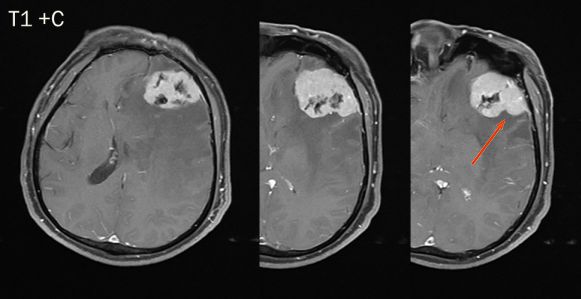

CASE 4

男,62 岁

右侧顶叶区混杂信号占位,T1、T2 内部条样低信号影,血管留空信号;增强可见明显强化,内部信号欠均匀,内见强化迂曲血管影。

诊断:右侧顶叶区血管外皮瘤